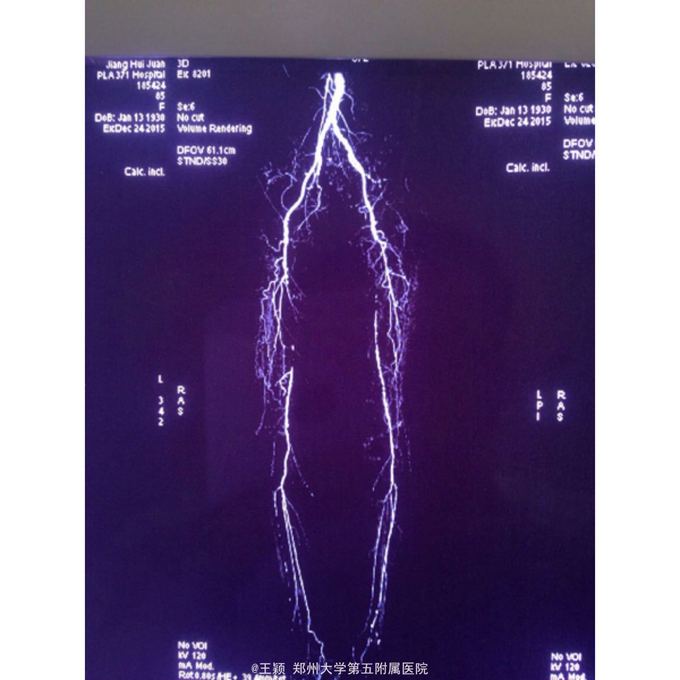

双下肢皮温低,皮色苍白,左足第五趾趾端坏死,右侧股动脉搏动可,左侧股动脉搏动弱,双侧掴动脉,胫前及胫后动脉搏动均未触及,CTA见图